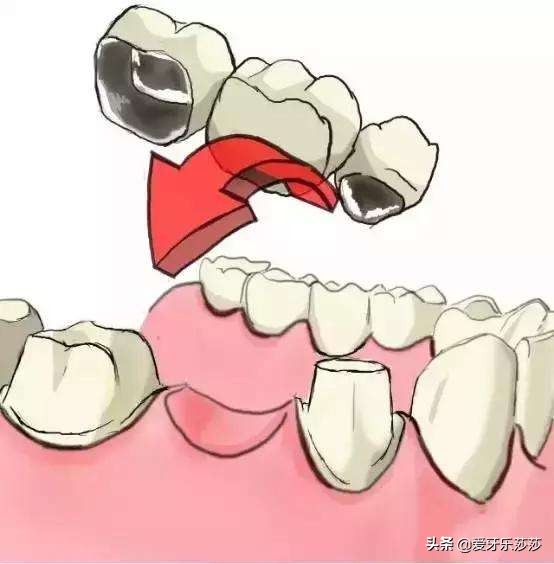

一般我们做的烤瓷冠大都分为单冠和连冠,连冠的烤瓷冠是无法单颗移动,会直接影响矫正效果。因此当小伙伴戴的是搭桥连冠烤瓷冠的话,则需要考虑拆除,等矫正牙齿后完成后再重新制作。若连冠烤瓷牙涉及到的位置是无需移动呢!,小伙伴则可以选择隐形矫正来移动其他牙齿。